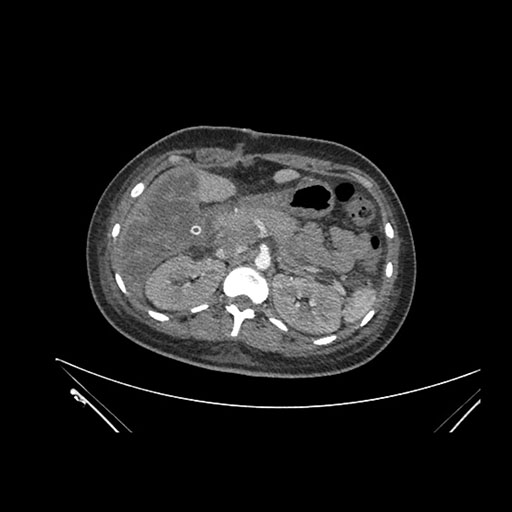

Axial Arterial

Axial Venous